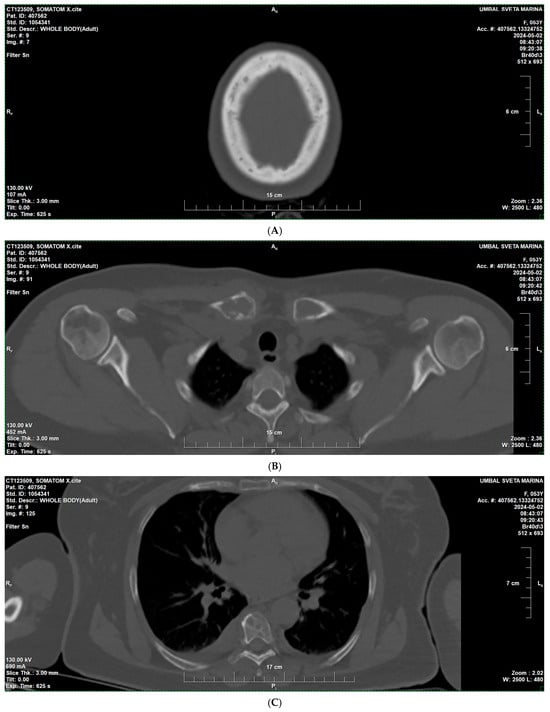

2. Case Presentation

3.2. Diagnostic Aspects